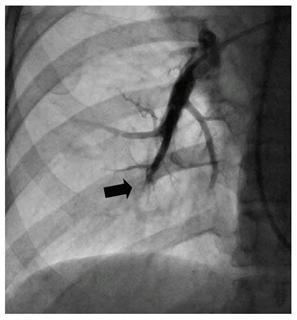

治療前、古い血栓で閉塞した肺動脈の末梢血管(国立循環器病研究センター提供)【拡大】